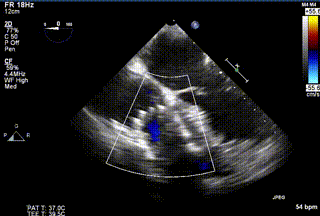

2021年12月24日,復旦大學附屬中山醫院葛均波院士團隊成功應用LuX-Valve Plus為一例極重度三尖瓣反流(TR)合并房顫、房缺的患者完成了經血管三尖瓣置換術,這是在前基礎上,本周完成的第三例經血管三尖瓣置換手術,葛均波院士、周達新教授等與心外科魏來教授、賴顥教授,心超室的潘翠珍教授、李偉教授及麻醉科的郭克芳教授共同完成了本周手術,均獲得圓滿成功!患者術后超聲顯示無TR,臨床癥狀明顯改善。本周手術的成功也為LuX-Valve Plus救治性臨床研究添上了濃墨重彩的一筆。

三例患者入院后,葛均波院士團隊周達新教授、潘文志教授、張源博士、陳莎莎博士及心超室的潘翠珍教授、李偉教授對患者的情況進行詳細評估和討論,最終決定為三例患者選擇LuX-Valve Plus40mm、50mm和50mm型號的瓣膜進行手術治療。手術后即刻拔除氣管插管,術后患者三尖瓣反流癥狀得到顯著改善,復查心超結果顯示人工三尖瓣瓣膜支架固定穩定,瓣葉關閉形態未見異常,未見明顯反流。